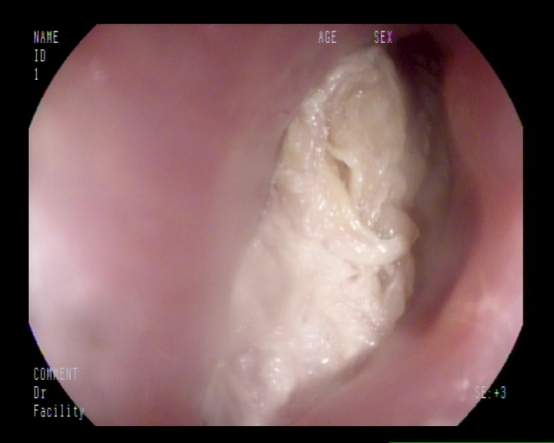

麻醉完成后,胃镜下可见食道上端入口处横卧着团块状食物堵住了整个食管入口,初步判断为鸡肉,距离门齿仅15cm。梁政主治医师在胃镜下通过活检钳、爪钳、圈套器试图把食物取出,初步判断为鸡肉。但因鸡肉块状已局部消化,难以整块取出,稍有不慎容易刺破食管或滑入气管,后果不堪设想,情况十分危急。

在消化内科梁政主治医师、麻醉科许永健主治医师、何少玲主管护师、以及马宗宝护师的合作下,鸡肉残渣及鸡骨被小心翼翼地顺利完整取出,经胃镜检查,未发现有新的粘膜受损。